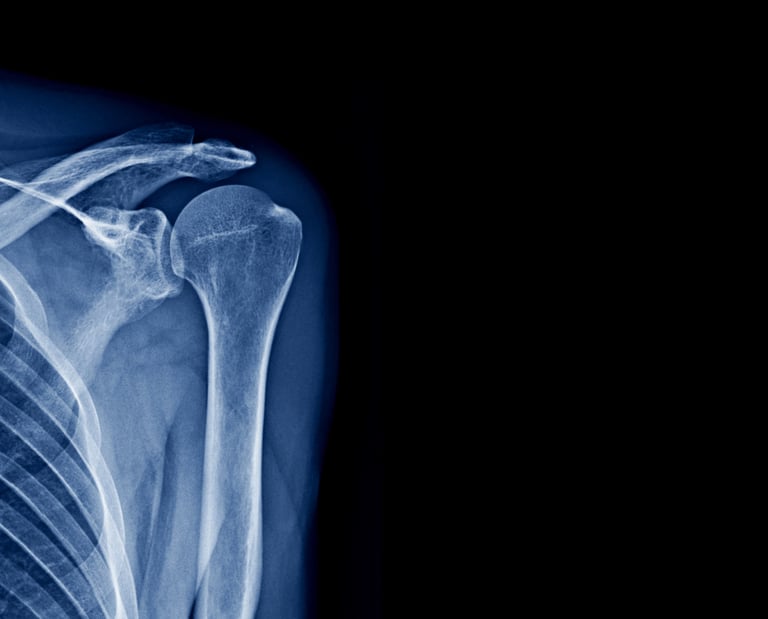

Χειρουργική Άνω Άκρου

Η χειρουργική αποκατάσταση του άνω άκρου περιλαμβάνει την αντιμετώπιση καταγμάτων, αρθρώσεων και παθήσεων με στόχο την πλήρη αποκατάσταση της λειτουργικότητας και την επιστροφή σε καθημερινές δραστηριότητες.